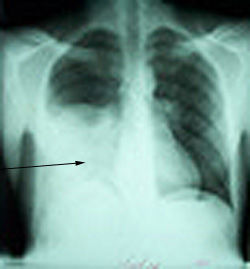

1. Chest X-Ray